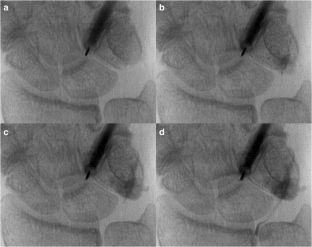

Fig. 1

Fig. 2

Fig. 3

Fig. 4

Fig. 5

Fig. 6

Fig. 7

Fig. 8